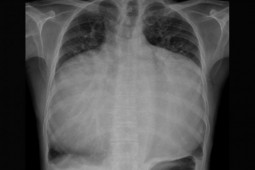

Theo BS Đặng Khải Minh, khoa Chấn thương Chỉnh hình Bệnh viện Nhi Đồng 1, thông thường bệnh nhi bị ngực lõm được xem xét chỉ định phẫu thuật từ 8 tuổi. Tuy nhiên, trường hợp bé T. vùng ngực của bé lõm rất sâu, xương ức và xương sống gần như chạm vào nhau dẫn đến tim phổi của bé đều bị chèn ép. Bên cạnh đó, bé còn bị kén khí phổi bên phải, dẫn đến viêm phổi tái phát liên tục.

Tình trạng lõm ngực nặng khiến tim phổi của bệnh nhi bị chèn ép đe dọa tính mạng

Được biết, đây là ca lõm ngực nhỏ tuổi nhất, mức độ lõm cũng nặng nhất từ trước đến nay tại Bệnh viện Nhi đồng 1. BS Đào Trung Hiếu, nguyên Phó giám đốc Bệnh viện Nhi Đồng 1 cho biết, bên cạnh tình trạng viêm phổi tái đi tái lại, trẻ còn bị hở van tim nặng do tim bị chèn ép, khó có thể phẫu thuật sửa chữa van tim.